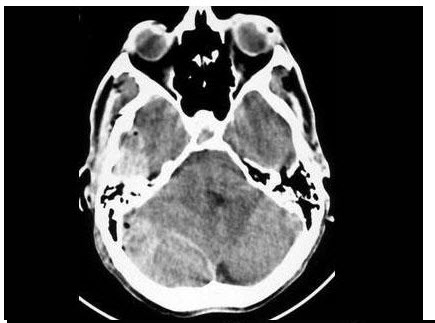

159、单项选择题

女,12岁,头痛、恶心、呕吐1周,平扫CT检查如图

A.胶质瘤

B.脑膜瘤

C.室管膜瘤

D.髓母细胞瘤

E.胶质母细胞瘤

177、单项选择题

A.前颅窝

B.中颅窝

C.后颅窝

D.脑自质

E.脑皮质

178、单项选择题 关于门静脉瘤栓的描述,不正确的是()